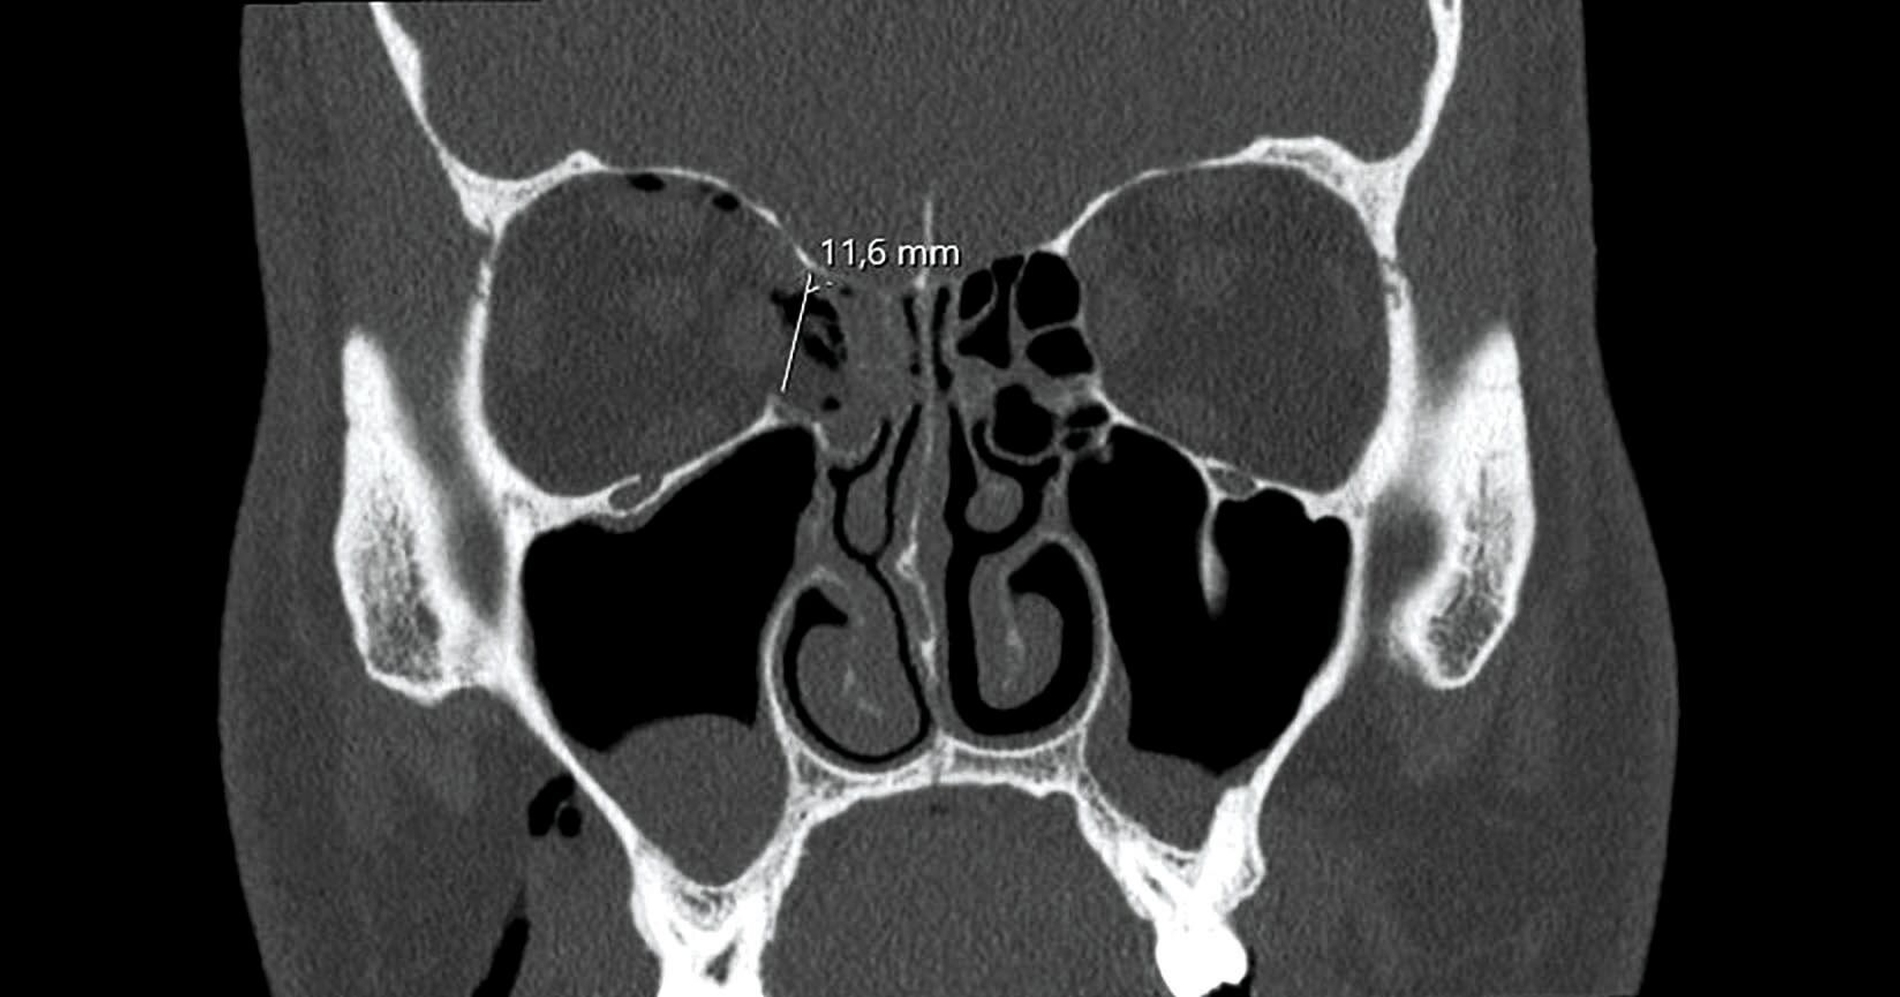

Nach der eingehenden klinischen Untersuchung wurde zur weiteren Diagnostik eine Computertomografie (CT) durchgeführt, die die Verdachtsdiagnose einer Fraktur der rechten Orbita bestätigte. Die CT-Bilder zeigten eine Fraktur der dünnen seitlichen Wand des Siebbeinlabyrinths (Lamina papyracea) mit Herniation des orbitalen Fettgewebes sowie eine geringfügige Vorwölbung des Musculus rectus lateralis in den Knochendefekt. Zudem war ein ausgeprägtes Weichgewebsemphysem sichtbar (Abbildung 1). Weitere Frakturen konnten ausgeschlossen werden.